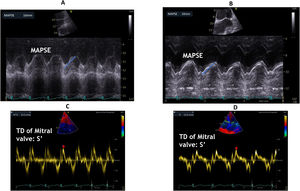

Mitral annular plane systolic excursion (MAPSE) (Fig. 2A and B):

It is measured by the use of M-mode echocardiography from four sites of the atrioventricular plane corresponding to the septal, lateral, anterior, and posterior walls using the apical four- and two-chamber views by M-mode echocardiography. The M-mode cursor should always be aligned parallel to the LV walls. The systolic excursion of mitral annulus should be measured from the lowest point at end-diastole to aortic valve closure (end of the T-wave on the electrocardiogram). MAPSE represents the amount of displacement of the mitral annular plane towards the apex and thus assesses the global change in size of the LV cavity (in the long-axis direction). The average normal value of MAPSE derived from previous studies for the four annular regions (septal, anterior, lateral, and posterior) ranged between 12 and 15 mm5,6 and a value of 8 mm was associated with a depressed LVEF (<50%) with a specificity of 82% and a sensitivity of 98%.5 In addition, a mean value for MAPSE of 7 mm could be used to detect an EF < 30% with a sensitivity of 92% and a specificity of 67% in dilated cardiomyopathy patients with severe congestive heart failure.6 It is of note that the association between MAPSE and EF is only valid in case of normal or dilated left ventricles7,8 while the correlation is rather poor in patients with LV hypertrophy.9

Tissue Doppler peak systolic wave at the mitral lateral annulus (S′) (Fig. 2C and D):

Tissue Doppler imaging enables measurements of atrioventricular annular and regional myocardial velocities, and may be more sensitive than conventional echocardiography in detecting abnormalities of LV systolic and diastolic function.10 Two previous studies showed that there was a close correlation between systolic annular displacement directly measured by M-mode and that indirectly estimated by temporal integration of velocities measured by either pulsed tissue Doppler or colour Doppler in healthy subjects.11,12 Similar results were reported, showing a significant correlation between S′. and MAPSE both at rest and during exercise in heart failure patients with preserved LVEF13 S′ value >10 cm/s is correlated to preserved LVEF, 6–8 cm/s corresponds to altered LVEF between 30 and 45%, and S′ value <6 cm/s is associated with LVEF < 30%.14